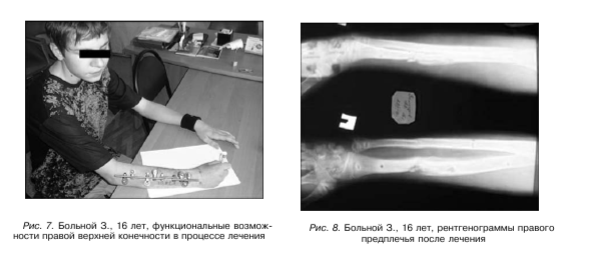

Аппараты демонтированы через 3,5 месяца. Ось предплечья правильная. Движения в локтевом и лучезапястном суставах в полном объеме (рис. 8).